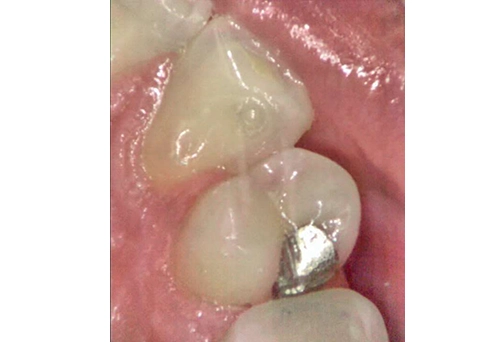

Caries lesion on a mesial surface of UR5, barely visible on (1) Intraoral camera image and a (2) bitewing X-ray, can be clearly identified on the (3) iTero™ NIRI technology (Near Infra-Red Imaging) images. (4) Caries lesion confirmed clinically. Images are courtesy of Dr. Einfeldt.

Reviewing scans with an intraoral camera and iTero™ NIRI technology (Near Infra-Red Imaging) images that iTero™ takes automatically is what I always do. Sometimes, the X-rays are not ideal if the angle is not right or an overlap occurs, so the NIRI in my hands is more sensitive. NIRI has helped me find caries that X-rays didn’t show. Despite years of experience, magnification, and good light, interproximal caries are hard to detect. NIRI images from iTero highlight it and help me decide when to treat it.